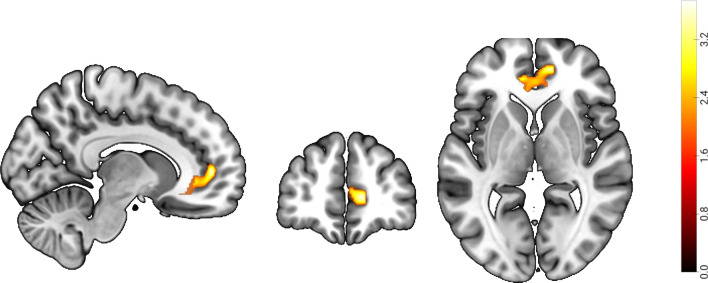

Procrastination is universally acknowledged as a problematic behavior with wide-ranging consequences impacting various facets of individuals' lives, including academic achievement, social accomplishments, and mental health. Although previous research has indicated that future self-continuity is robustly negatively correlated with procrastination, it remains unknown about the neural mechanisms underlying the impact of future self-continuity on procrastination. To address this issue, we employed a free construction approach to collect individuals' episodic future thinking (EFT) thoughts regarding specific procrastination tasks. Next, we conducted voxel-based morphometry (VBM) and resting-state functional connectivity (RSFC) analysis to explore the neural substrates underlying future self-continuity. Behavior results revealed that future self-continuity was significantly negatively correlated with procrastination, and positively correlated with anticipated positive outcome. The VBM analysis showed a positive association between future self-continuity and gray matter volumes in the right ventromedial prefrontal cortex (vmPFC). Furthermore, the RSFC results indicated that the functional connectivity between the right vmPFC and the left inferior parietal lobule (IPL) was positively correlated with future self-continuity. More importantly, the mediation analysis demonstrated that anticipated positive outcome can completely mediate the relationship between the vmPFC-IPL functional connectivity and procrastination. These findings suggested that vmPFC-IPL functional connectivity might prompt anticipated positive outcome about the task and thereby reduce procrastination, which provides a new perspective to understand the relationship between future self-continuity and procrastination.

拖延被普遍认为是一种有问题的行为,会对个人生活的各个方面产生广泛的影响,包括学习成绩、社会成就和心理健康。尽管以往的研究表明,未来自我连续性与拖延症呈显著负相关,但未来自我连续性对拖延症影响的神经机制仍是未知数。为了解决这个问题,我们采用了一种自由构建的方法来收集个体对特定拖延任务的外显未来思维(EFT)想法。接下来,我们进行了体素形态计量(VBM)和静息态功能连接(RSFC)分析,以探索未来自我连续性的神经基底。行为结果显示,未来自我连续性与拖延显著负相关,与预期积极结果正相关。VBM 分析显示,未来自我连续性与右侧腹内侧前额叶皮层(vmPFC)的灰质体积呈正相关。此外,RSFC 结果表明,右侧 vmPFC 和左侧下顶叶(IPL)之间的功能连接与未来自我连续性呈正相关。更重要的是,中介分析表明,预期的积极结果可以完全中介 vmPFC-IPL 功能连接与拖延之间的关系。这些研究结果表明,vmPFC-IPL功能连接可能会促使人们对任务产生预期的积极结果,从而减少拖延,这为理解未来自我连续性与拖延之间的关系提供了一个新的视角。